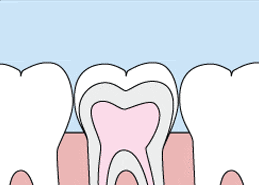

窝沟封闭就是用一种对人体无害通过光固化合成的有机高分子树脂材料,在牙齿的十字型窝沟内涂上,液态时它可渗入到牙齿表面的窝沟内,经光照后固化。隔绝口腔环境中的致龋因素对牙齿的侵害,形成一层保护性屏障,阻止细菌及食物残渣进入窝沟,就如同给牙齿穿上了一层保护衣和铠甲。

窝沟封闭不损伤牙体组织,只是将闭合材料涂布于牙冠咬合面、颊舌面的窝沟点隙,阻止致龋菌及酸性代谢产物对牙体的侵蚀,从而达到预防窝沟龋的目的。其原理是,液态的树脂在进入窝沟后固化变硬,形成一层保护性的屏障,覆盖在窝沟上,外面的致龋细菌不能再进入,从而达到预防窝沟龋的目的。窝沟封闭速度很快并且毫无痛苦。